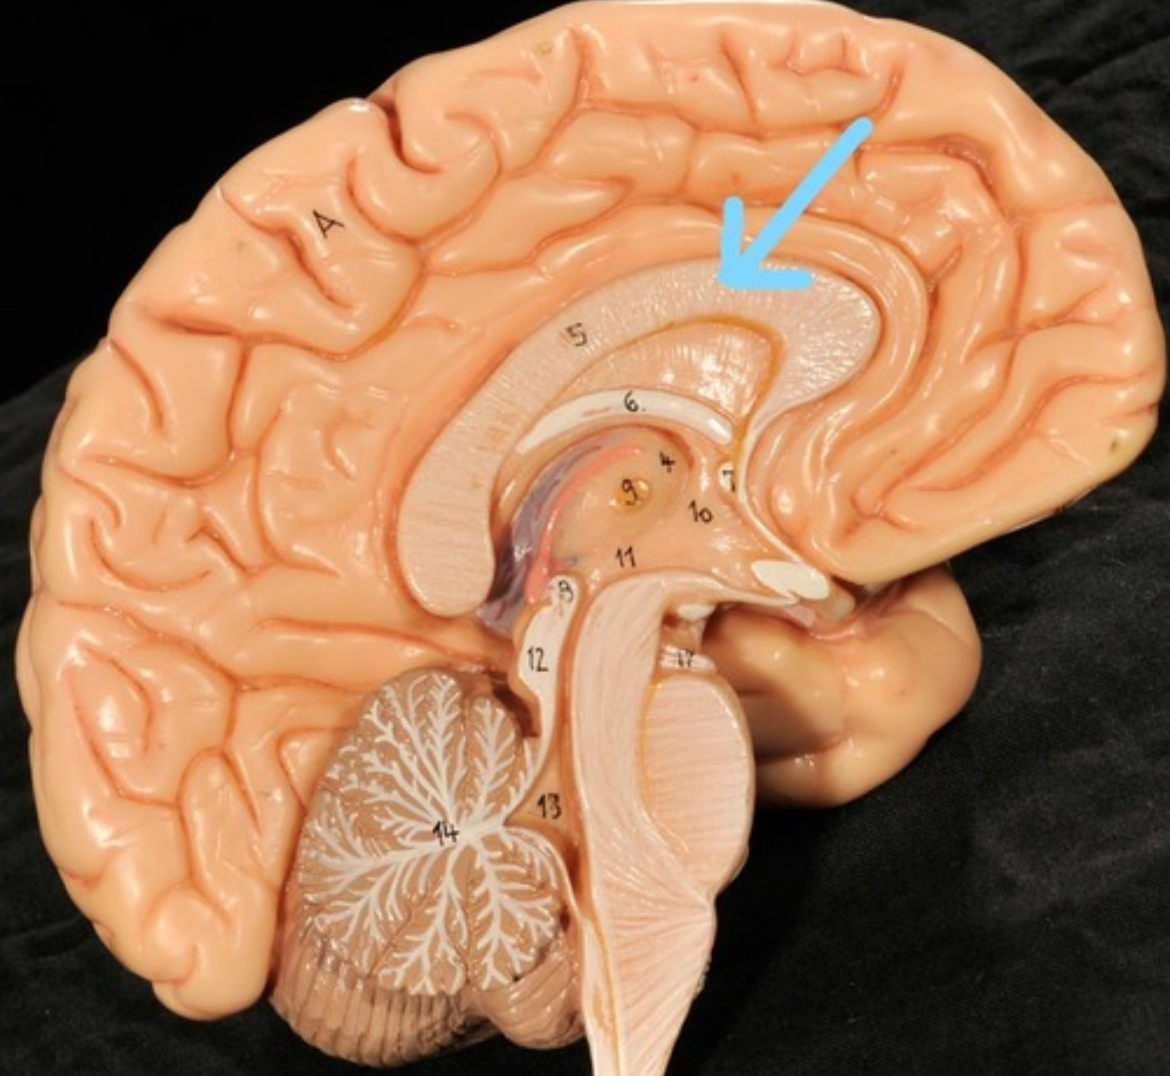

Corpus callosum

Diencephalon

Thalamus

3rd ventricle

Hypothalamus

Epithalamus (pink line)

Brain stem

Pons

Medulla oblongata

Choroid plexus of 3rd ventricle

Cerebral aqueduct (midrain)

4th ventricle

central canal